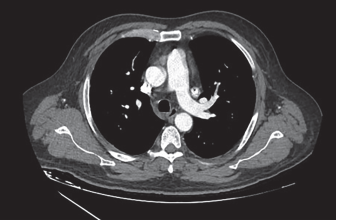

Se colocó un catéter Mahurkar sin complicaciones, pero en la radiografía de tórax figura 1 se observó una localización atípica. Por lo tanto, se solicitó una angiotomografía de tórax, la cual mostró imágenes relacionadas con la persistencia de la vena cava superior izquierda figuras 2 y 3, con el catéter venoso central en su interior, cuyo extremo se encontraba en el tercio distal vaso anómalo se originaba en la confluencia de la vena yugular interna izquierda y la vena subclavia izquierda, discurriendo inferiormente a la izquierda del arco aórtico y anterior al hilio pulmonar izquierdo, drenando finalmente en la aurícula derecha.

Figura 3 Angiotomografía de tórax venta na arterial, corte axial que muestra el catéter venoso central colocado en la vena cava superior persistente